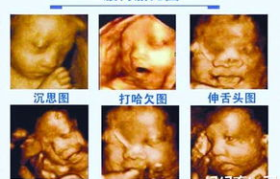

四维彩超作为孕期重要的产前检查项目,其价格因地区、医院等级和检查项目复杂度而异。本文将全面解析四维彩...